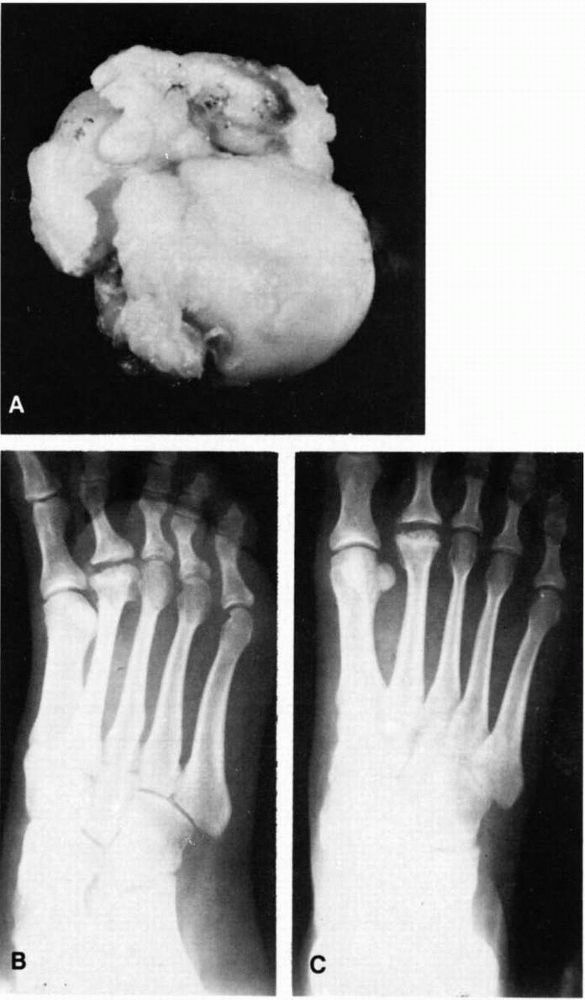

On the standing lateral view, the navicular has a decreased AP diameter

with evidence of varying amounts of flattening. Multiple centers of

ossification may be present. As mentioned previously, these

radiographic features may be a normal variation in as many as one-third

of children, particularly those who have late-onset ossification.

Therefore, the diagnosis of Köhler disease is made only with the

![]() |

FIGURE 20-26. Köhler disease or osteochondrosis of the tarsal navicular.